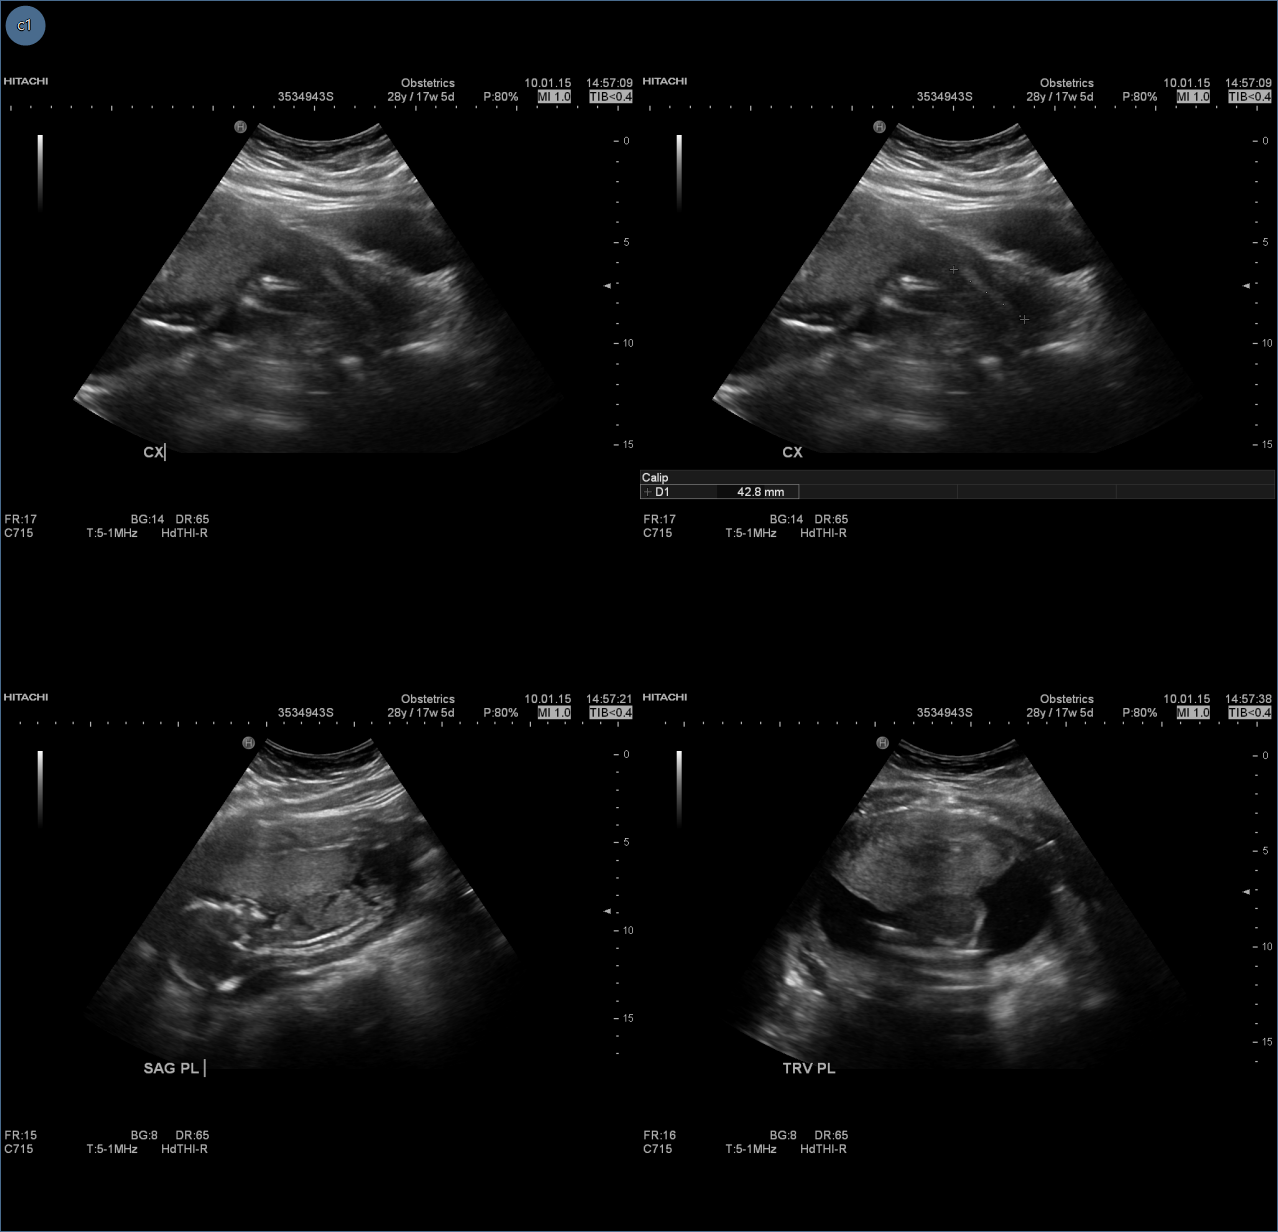

The Tiles matrix applies a tile pattern to a selected frame, controlling the number of images displayed in the frame. When the Tiles matrix

is selected in the tools group, a drop down panel appears that allows the user to draw a tile layout.

To apply a tiles matrix:

Select an image frame

Select the tiles matrix icon ![]()

Drag mouse to define tile layout

The selected image frame will now show images in the series as 2 x 2 tiles within the frame.